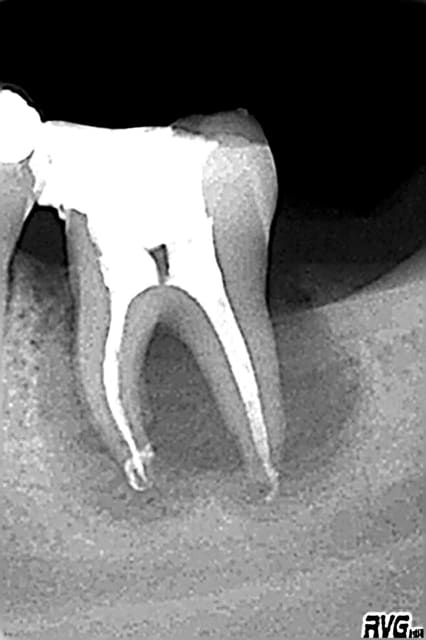

Est ce un fait exprès? Mais depuis mon retour, presque toute ma pratique tourne autour des reprises ENDO, et là, il faut que j'avoue toute l'admiration que j'ai pour les endodontistes exclusifs, c'est tout bonnement éreintant cette discipline, surtout lorsqu'on tombe sur des os!

Est-ce un fruit du hasard, mais les interventions que j'ai négociées représentent pratiquement tous les cas de figure qu'a traité Stéphane:

- fausse route bouchée au MTA

-instrument fracturé impossible à retirer, je suis passée à côté et je l'ai noyé dans la gutta chaude.

Et tout de même quelques racines domptées sans trop de difficultés!